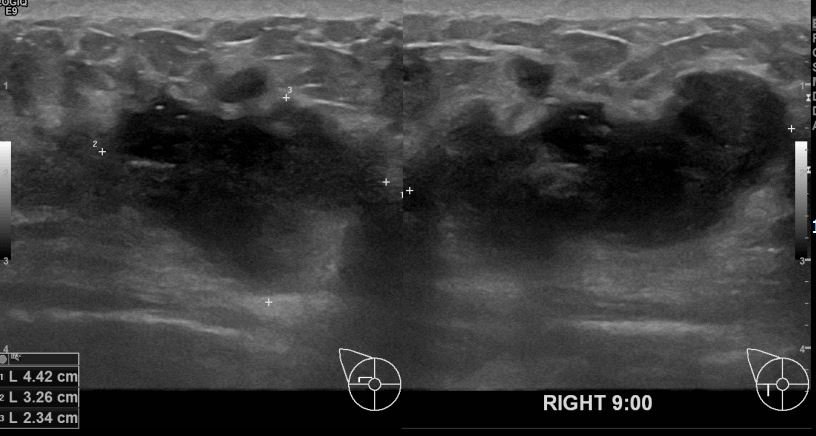

아산유외과 개원후 636번째 유방암진단

상기환자 외부검사상 이상소견으로 내원하신 30대여성으로 우측 유방의 의심스러혹

조직검사시행해 유방암 진단되었읍니다